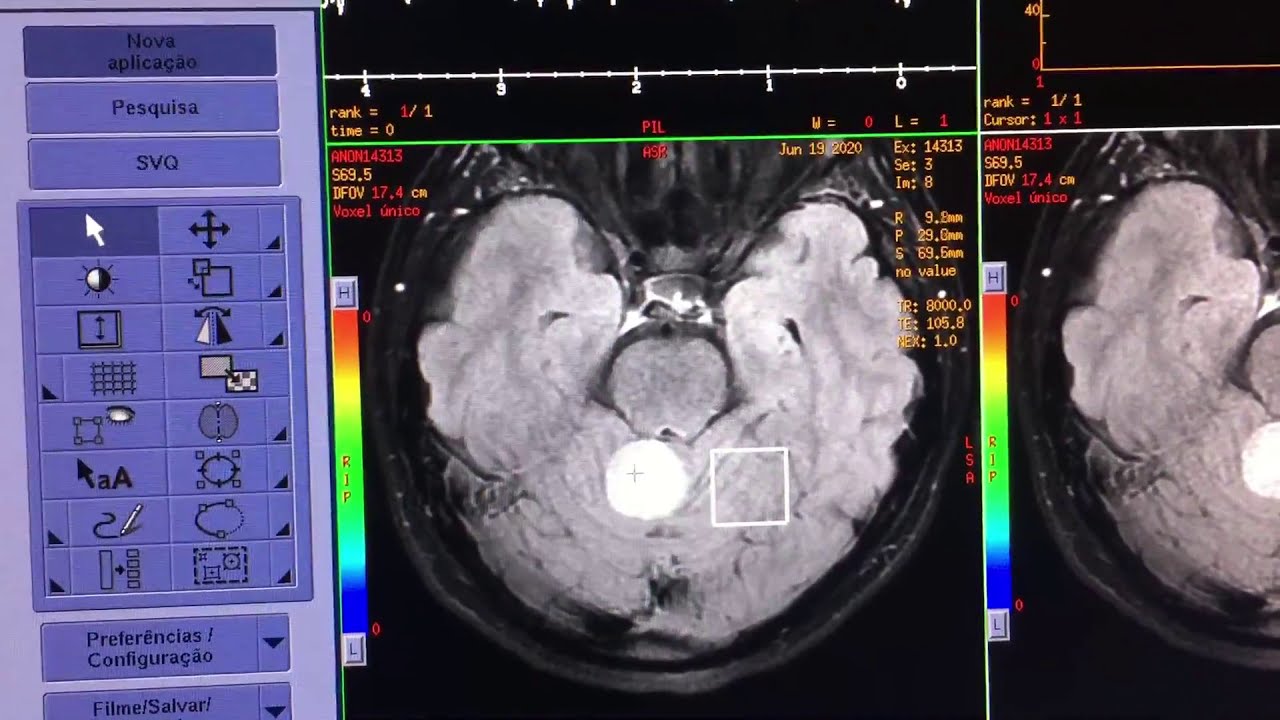

A espectroscopia por ressonância magnética (RM) é uma extensão da imagem convencional por RM que permite analisar o perfil químico dos tecidos. Em vez de apenas mostrar imagens anatômicas, ela revela informações sobre o metabolismo celular, sendo essencial para identificar alterações metabólicas precoces, principalmente no cérebro.

É indicada principalmente em investigações neurológicas, como tumores cerebrais, epilepsia, infecções, doenças degenerativas e metabolopatias. Ajuda a diferenciar lesões benignas de malignas, analisar extensão de infiltração tumoral e monitorar resposta a tratamentos.

A espectroscopia permite uma análise funcional complementar, agregando valor à imagem anatômica. Evita biopsias desnecessárias em alguns casos, melhora o planejamento cirúrgico e ajuda a definir melhor a conduta clínica.